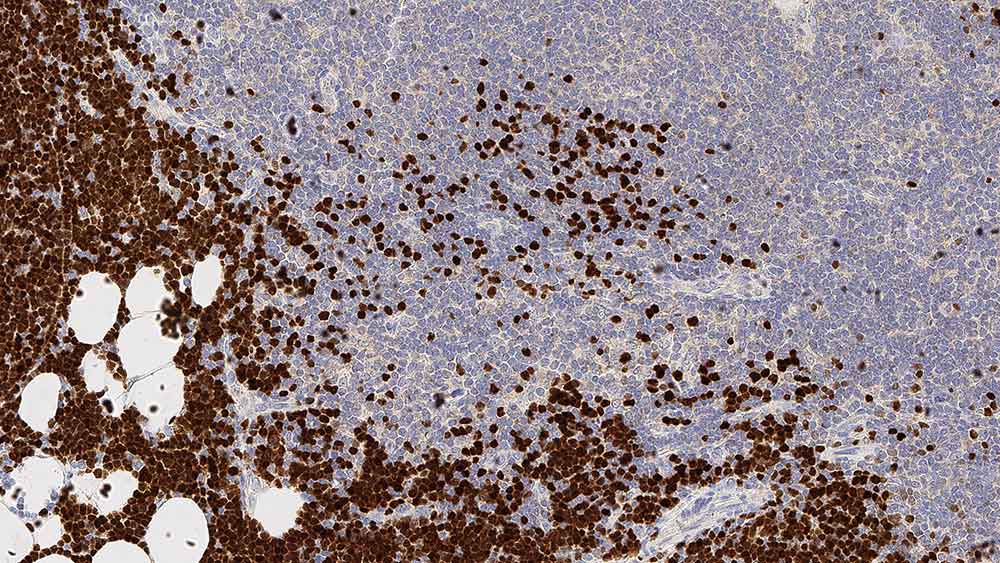

Human thymus: immunohistochemical staining for Terminal Deoxynucleotidyl Transferase. Note nuclear staining for cortical thymic lymphocytes. Terminal deoxynucleotidyl transferase: clone SEN28

Die Expression von TdT wird in den primitiven T- und B-Lymphozyten des normalen Thymus und Knochenmarks beschrieben.

Die Identifizierung von TdT-positiven Zellpopulationen in den primären und sekundären lymphatischen Organen bei der Reifung des Immunsystems ist ein Zielgebiet der Forschung, doch gilt das besondere Interesse dem Auftreten einer starken enzymatischen Aktivität in den Leukozyten und im Knochenmark bei bestimmten Leukämieformen.

Eine frühe und präzise Differenzierung des lymphoblastischen Lymphoms ist von entscheidender Bedeutung. TdT wird bei lymphoblastischen Lymphomen und Leukämie exprimiert.

Es wurde festgestellt, dass die Bestimmung der TdT-Expression von größtem Wert ist, wenn sich histologisch die Differenzierung zwischen lymphoblastischem Lymphom und Burkitt-Lymphom als schwierig erweist.